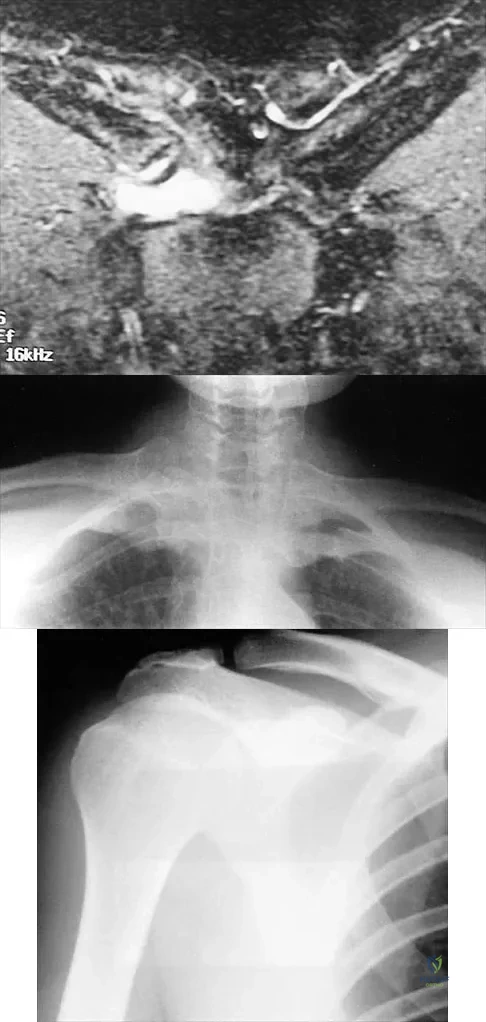

A 43-year-old former professional hockey player reports severe pain in his chest after being checked from the side in a pick-up hockey game. An MRI scan and plain radiographs are shown in Figures 25a through 25c. What is the most likely diagnosis?

Explanation

A 52-year-old woman reports mild pain localized to the left sternoclavicular joint. History is notable for chronic renal failure requiring dialysis for the last 5 years. A clinical photograph, chest radiograph, and bone scan are shown in Figures 58a through 58c. What is the most likely diagnosis?

Explanation